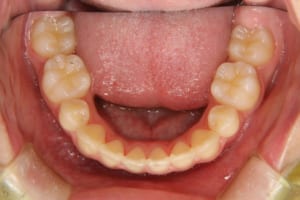

治療前

| 主訴 | 八重歯の生え方が気になる |

| 抜歯および非抜歯 | 上顎:両側第一小臼歯 下顎:右側第二小臼歯 先天欠如:下顎左側第二小臼歯 乳歯:下顎左側第二乳臼歯 |

| その他/備考 | 上の犬歯が生えるためのスペースが全くない状態でした。放置すると重度の八重歯になることが想定されるケースです。 今回はあごの成長も利用しながら治療をするために、早めに後期治療(大人の矯正治療)に移行しました。 治療後レントゲン写真を見たところ、上顎前歯に若干の歯根吸収を認めました。 |